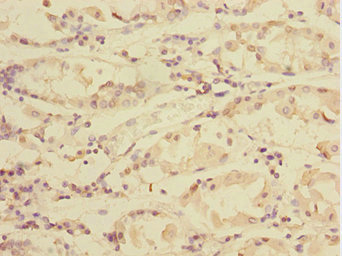

Immunohistochemistry of paraffin-embedded human gastric cancer using CSB-PA847679ESR1HU at dilution of 1:100